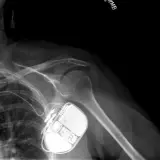

PACS์—์„œ ๊ธฐ๋Œ€ํ•  ์ˆ˜ ์žˆ๋Š” ๋ชจ๋“  ๋„๊ตฌ๋ฅผ ๊ฐ–์ถ˜ ์™„์ „ํ•œ ์ธํ„ฐ๋ž™ํ‹ฐ๋ธŒ ์ฆ๋ก€ — ์Šคํฌ๋กค, ์œˆ๋„์šฐ ์กฐ์ ˆ, ํ™•๋Œ€/์ถ•์†Œ, ํŒจ๋‹, ๊ณ„์ธก, ROI, ์ „์ฒด ํ™”๋ฉด ๋ชจ๋“œ๊นŒ์ง€ ์ง€์›ํ•ฉ๋‹ˆ๋‹ค.

์ฃผ์š” ์†Œ๊ฒฌ์„ ์ฆ๋ก€์— ์ง์ ‘ ํ‘œ์‹œํ•˜๋Š” ํ’๋ถ€ํ•œ ์ฃผ์„์ด ํฌํ•จ๋˜์–ด ์žˆ์Šต๋‹ˆ๋‹ค. ์ฆ๋ก€ ์„ค๋ช…์˜ ์—ฐ๊ฒฐ๋œ ์†Œ๊ฒฌ์„ ํด๋ฆญํ•˜๋ฉด ์Šค์บ” ๋‚ด ์ •ํ™•ํ•œ ์œ„์น˜๋กœ ๋ฐ”๋กœ ์ด๋™ํ•ฉ๋‹ˆ๋‹ค.